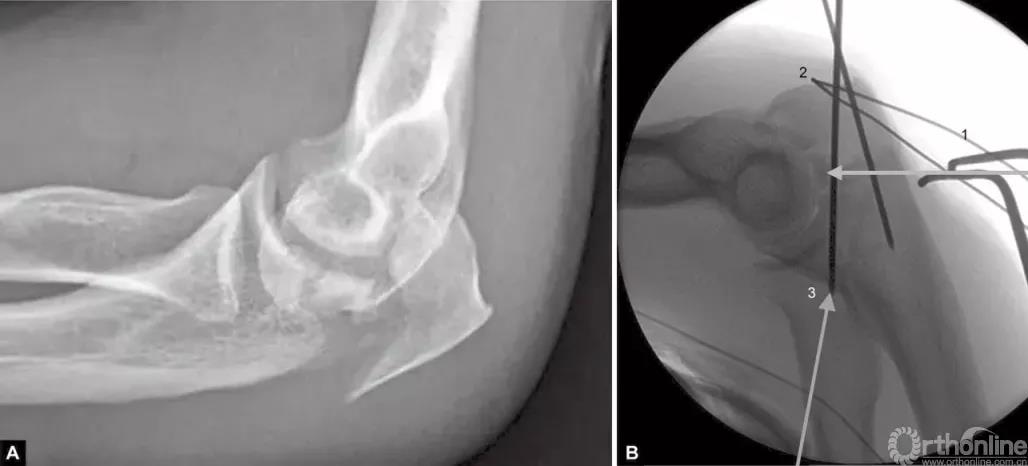

当存在鹰嘴关节面部分压缩时,必须将其对应肱骨滑车抬高复位。在三头肌止点用钢丝牵开鹰嘴尖端(图4),复位压缩骨折,用细克氏针将其推靠在肱骨滑车上维持位置。克氏针必须紧贴压缩骨折部位的软骨下骨来维持位置。此时,用高质量的侧位X线片检查来确定压缩骨折的复位,克氏针的位置是否良好是非常必要的。另一种方法是采用松质骨植骨来支撑复位的压缩骨折。

图4A和B(1)将鹰嘴拉下复位关节内松动的骨片,用横向箭头所示细克氏针,将其推挤在滑车上维持复位;(2)钢丝环穿过三头肌止点周围将鹰嘴拉下;(3)克氏针紧贴软骨下骨插入支撑松动的关节内骨片(给向箭头所示克氏针)